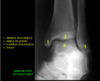

Medial malleolus

2

Tibial Plafond

3

Lateral malleolus

4

Talus